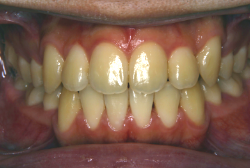

叢生(そうせい)

凸凹な歯並びのことを叢生といいます。矯正歯科に来院する患者様の主訴の中で、最も多いのが「配列の凸凹を真っ直ぐにしたい」というものです。歯の大きさと顎の大きさの調和がとれていないことが原因です。

凸凹を主体としたケースの場合、当院の平均治療期間は18ヶ月ですので、このケースは少し長めに経過しました。理由の一つは凸凹の程度がかなり重症だったと言うことですが、もう一つは、右下第2大臼歯が45度くらい前傾していたため、それを整直化させるために時間を要したと考えています。いずれにしても最終結果は大変よい状態と思います。

治療前は並びが乱れて見た目が悪いというのはもちろん問題ですが、歯科医学的に一番困るのは噛み合わせが悪いという点です。上下の犬歯(3番目の歯)は、上下的に離れた位置にあるため接触することができません。つまり歯としては存在していても、歯としては機能していないということです。